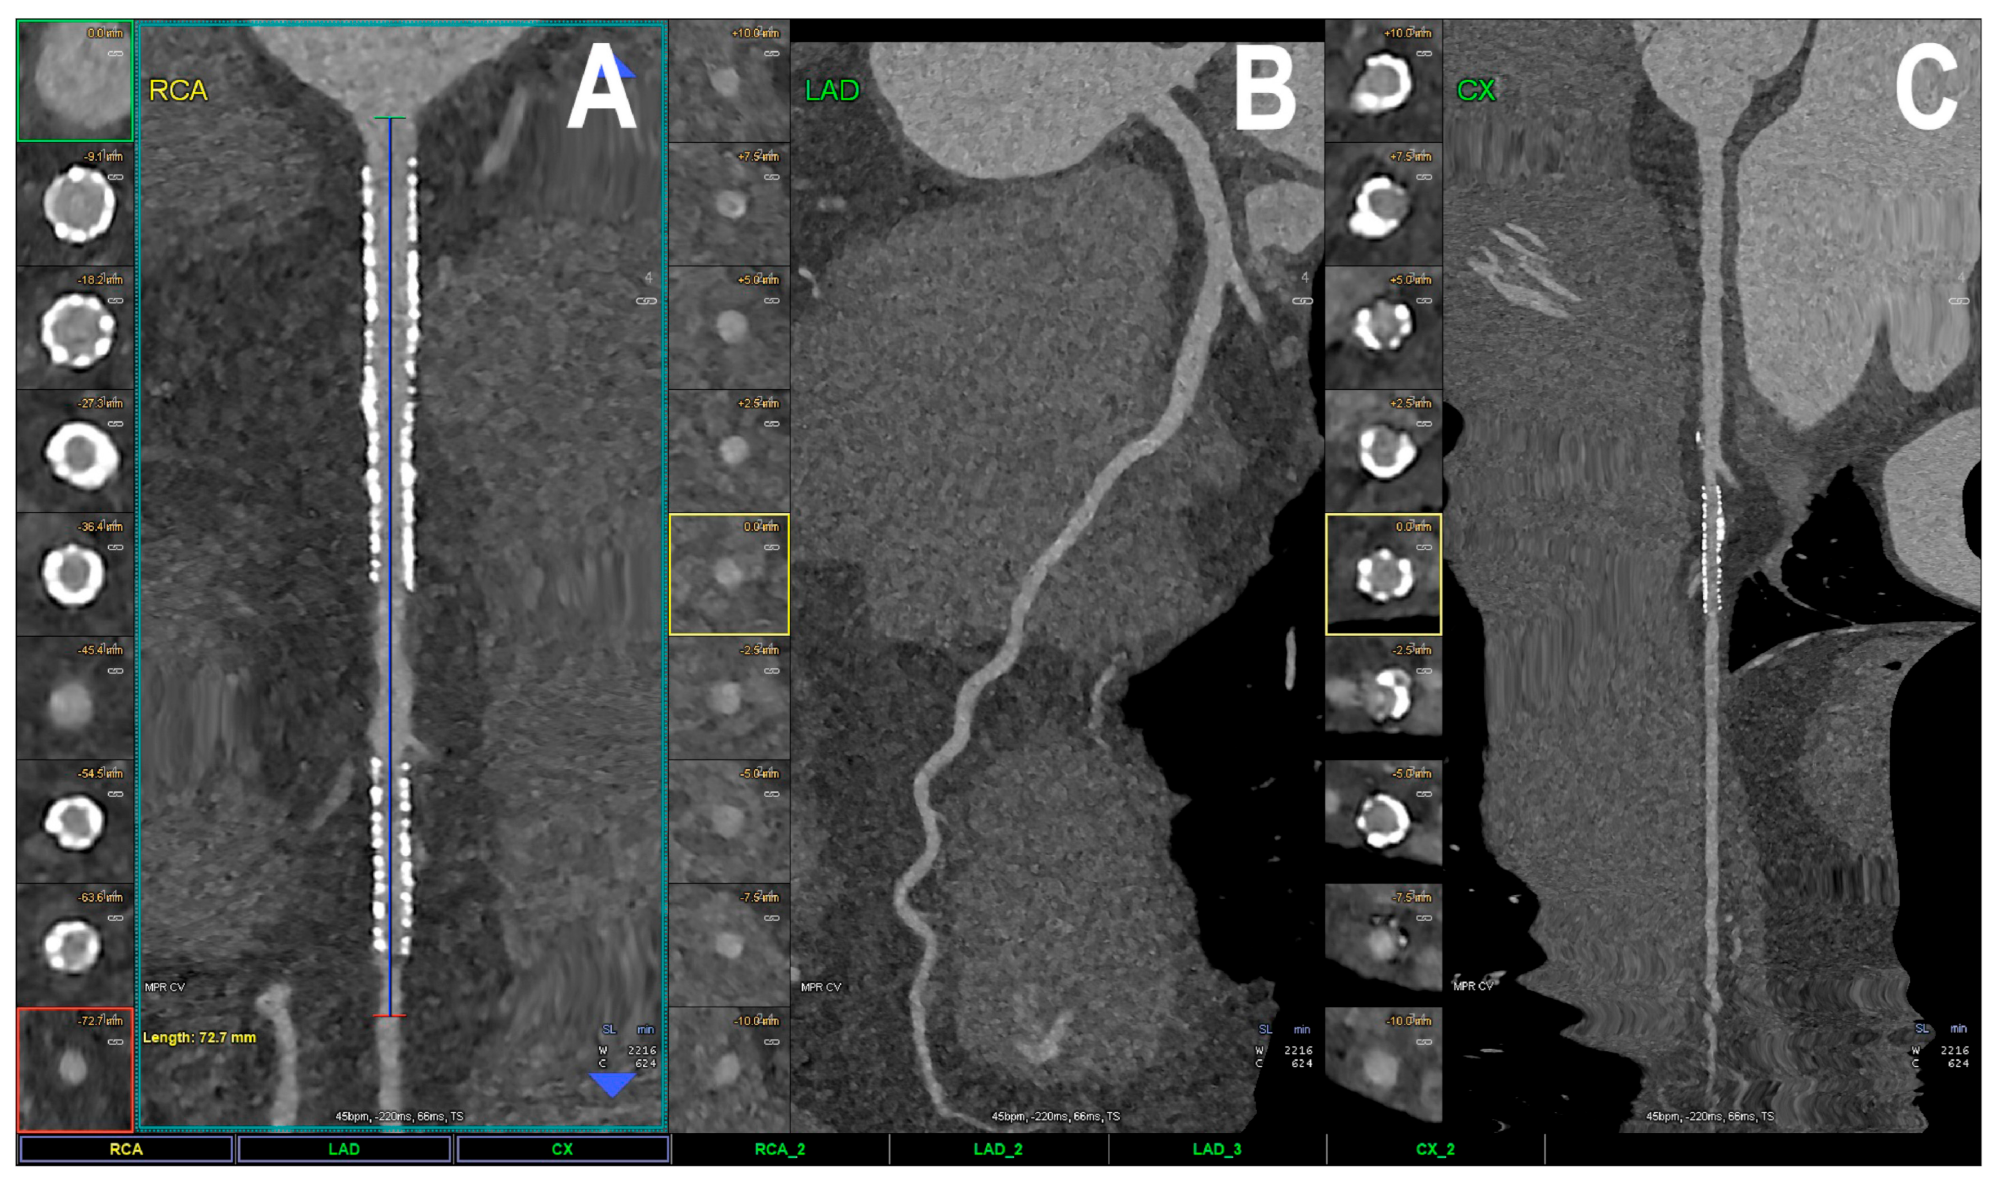

- Boccalini, S.; Si-Mohamed, S.A.; Lacombe, H.; Diaw, A.; Varasteh, M.; Rodesch, P.A.; Villien, M.; Sigovan, M.; Dessouky, R.; Coulon, P.; et al. First in-Human Results of Computed Tomography Angiography for Coronary Stent Assessment with a Spectral Photon Counting Computed Tomography. Investig. Radiol. 2022, 57, 212–221. [Google Scholar] [CrossRef] [PubMed]